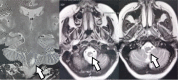

Results: Our study showed NMOSD as 9.37% of all demyelinating diseases registered in. It occurred predominantly in women (81%) and non-white individuals (83.4% had self-declared mixed skin color), and the median age at onset was 48 years. Amerindian ancestry was significantly higher (68.75%) than others. Longitudinally extensive transverse myelitis (LETM) alone ≥3 vertebral segments (35%) and optic neuritis (ON) alone (35%) were the most common onset manifestations. The median length of time from disease beginning to study enrollment was 48 months. A relapsing course and moderate disability (Expanded Disability Status Scale (EDSS) 3.0-4.0) were most commonly observed. The worst neurological impairments, characterized by EDSS>4.5, occurred more frequently in males (44.5% among men versus 20.5% among women). The majority of the patients had been receiving immunosuppressive treatment with azathioprine since the diagnosis of NMSOD: 77% (37) had a good therapeutic response. The prevalent outcome (84%) was permanent disability: 52% became physically handicapped; 54% had permanent visual impairment (25% with bilateral and 75% with unilateral amaurosis) and 30% had sphincter disability (82% with neurogenic bladder and 18% with ostomy).

Conclusion: The estimated prevalence of NMOSD in Goiás is 0.79/per 100,000 inhabitants. The predominant phenotype comprises women, non-whites, onset in the fourth decade of life, relapsing course, and permanent moderate disability. Our study was the first on the epidemiology of NMOSD in Goiás, where NMOSD predominantly correlates with Amerindian ancestry.